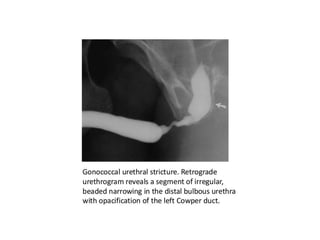

This document discusses the considerations and precautions for retrograde urethrography (RGU), noting that local anesthetic may cause issues such as mucosal edema. It highlights the need for antibiotic coverage due to potential complications like extravasation during contrast injection, and touches upon the role of cystography in pelvic fractures, indicating it can often be safely omitted. Additionally, it reports on complications related to urinary tract infections and reactions to contrast media, offering recommendations for patient management.